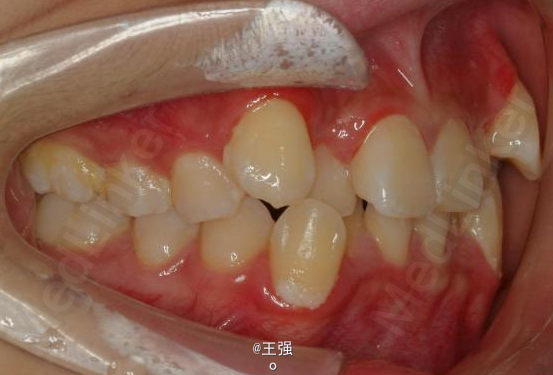

在临床上,我们常常会遇到亚类病例,对于亚类病例,有时需要不对称拔牙,常见的不对称拔牙方法有:上颌对称,下颌数目对称但是位置不对称。还有上颌对称,但是下颌数目不对称。其目的就是为了取得尽可能理想的尖窝对应咬合关系 该病例右侧是中性关系,左侧是中性偏远中关系,上颌中线正,下颌中线左偏约1mm。左侧磨牙关系距离中性关系约差2mm左右。如果采用对称性拔除下颌左右四,我们面临的问题是,一、如何保证矫治后上下中线一致,二、如何保证左侧磨牙关系矫治后为中性关系。治疗过程中势必会用到不对称牵引。我个人认为除非是功能性的因素,矫治过程中最好不要用不对称牵引。 关于中线和磨牙关系的问题,我认为应在矫治计划制定时就应考虑到,而不是等到矫治第三阶段所谓精细调整阶段再来解决。事实上到了这个阶段采用了不对称的牵引,即使暂时取得了中线对齐的矫治目的也是不稳定的。 这个病例,用了不对称的拔牙,右下拔四,左下拔五。下颌牙齿在漂移的过程中(几乎没有外来力量),下前牙自然就会向右比向左多漂移一些,中线在下颌还没有开始矫治时就对齐了,左下六因没有五的存在,自然就向近中多漂移一些,和上颌六形成中性关系。接下来的矫治就会非常简单,而结果自然也非常稳定。